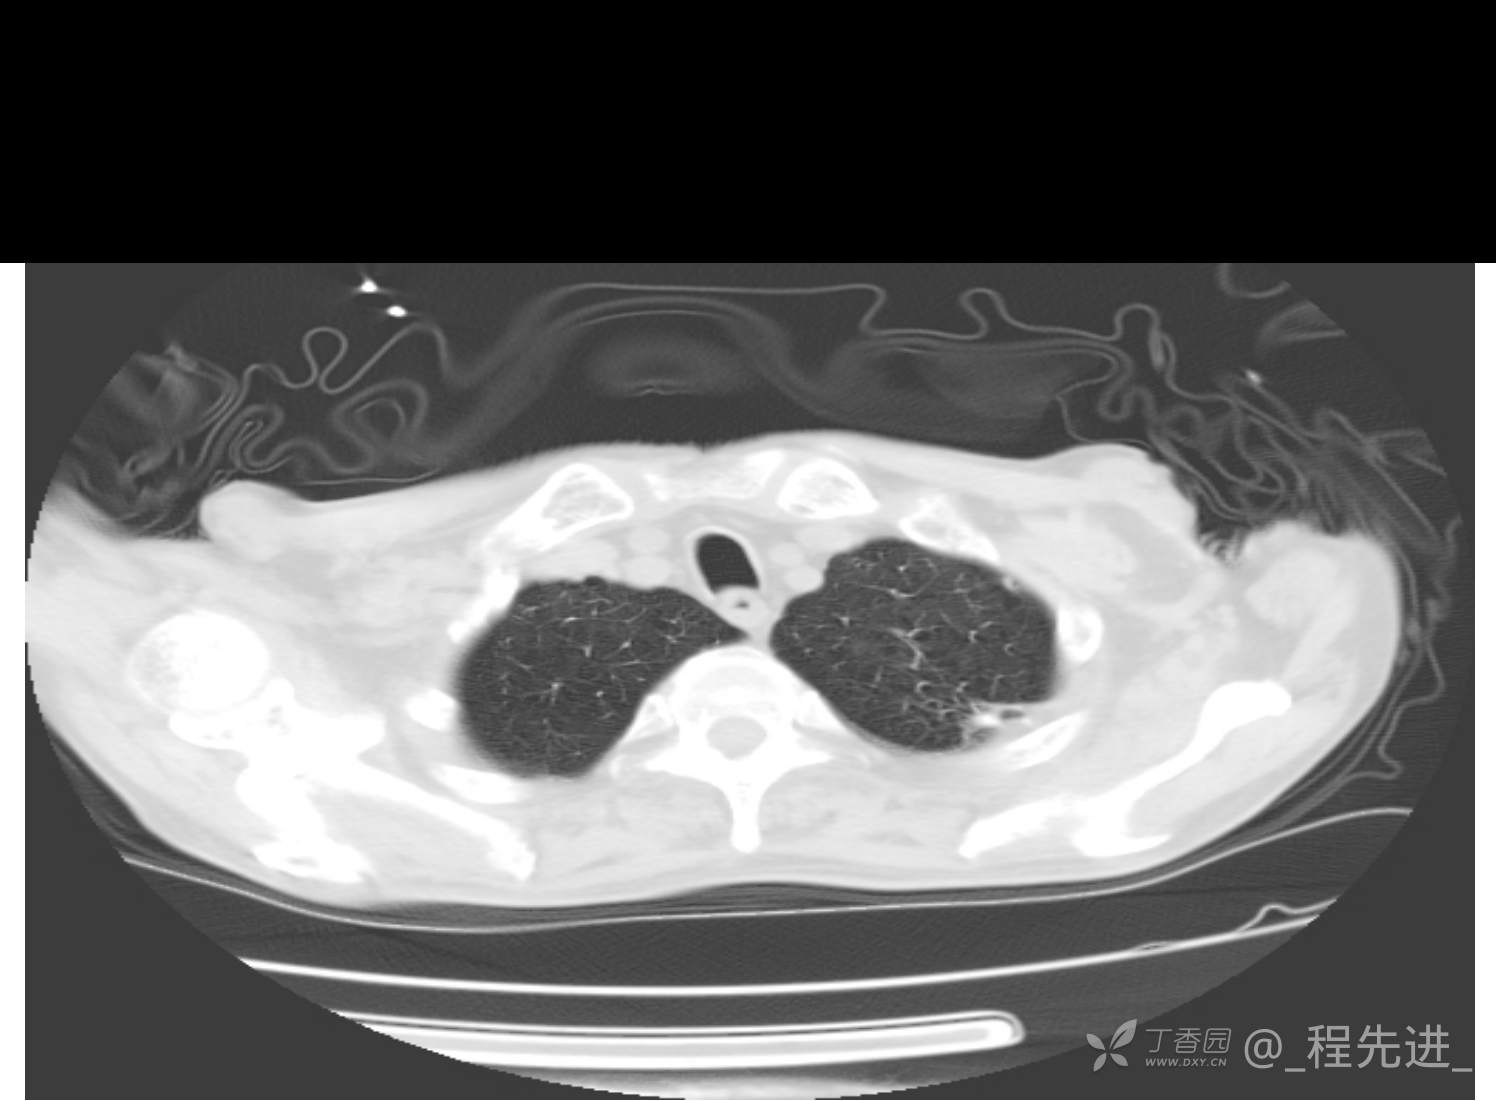

患者性别:男

患者年龄:81岁

简要病史:反复咳嗽、咳痰20余年,加重1周。两肺呼吸音低,可闻及散在干湿啰音。